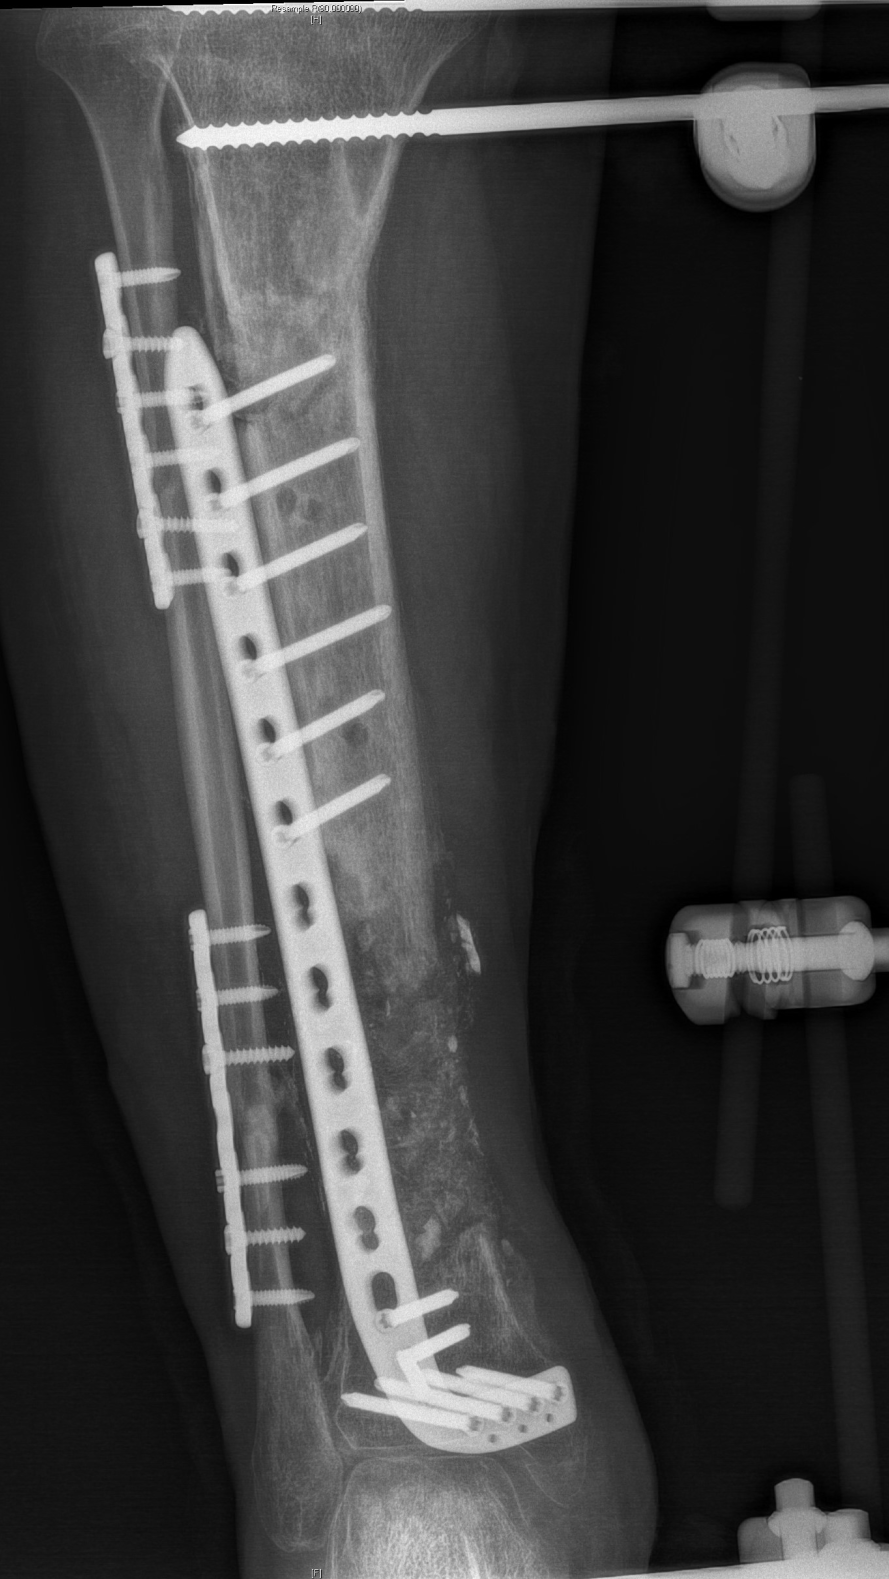

1、骨水泥植入

徐杨主任医师介绍,对于肢体毁损伤后期合并感染患者,保肢最大的难题是清创及骨与软组织重建,masquelet技术能够形成骨水泥诱导膜,不但能起到屏障作用,还含大量微血管,丰富血供,并能分泌各种促骨生长因子,具有成骨快、愈合率高的优点。尤其适合治疗长节段、严重感染性骨缺损病例。